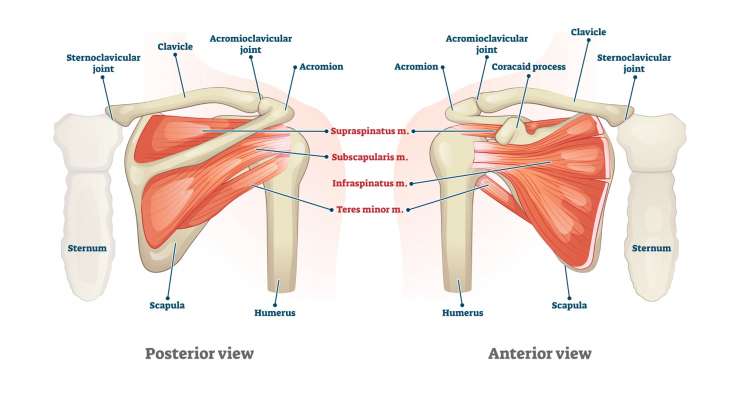

повреждение вращательной манжеты

Повреждение вращательной манжеты приводит к боли и потере функциональности плеча. В зависимости от результатов обследования, профессор, доктор медицины Франк Мартешлегер лечит это заболевание консервативным методом или с помощью артроскопии, проводя точную реконструкцию сухожилий.

Спектр лечения, предлагаемый профессором, доктором медицины Франком Мартешлегером в Мюнхене, охватывает все заболевания и травмы плеча – от вывиха AC-сустава и кальциевого плеча до артроза плеча (оартроза), разрывов вращательной манжеты и нестабильности плеча. Также дифференцированно диагностируются и индивидуально лечатся субакромиальный импинджмент, плечевой периартрит, травмы двуглавой мышцы, бурситы или переломы плечевого пояса. В зависимости от степени тяжести применяются консервативные методы, артроскопические вмешательства или открытые операции. Целью любого лечения является восстановление подвижности плеча, облегчение боли и обеспечение долгосрочной функции сустава — для улучшения качества жизни и избавления от боли в повседневной жизни.